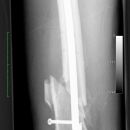

Fraktur Osteosynthese

Femurschaftfraktur